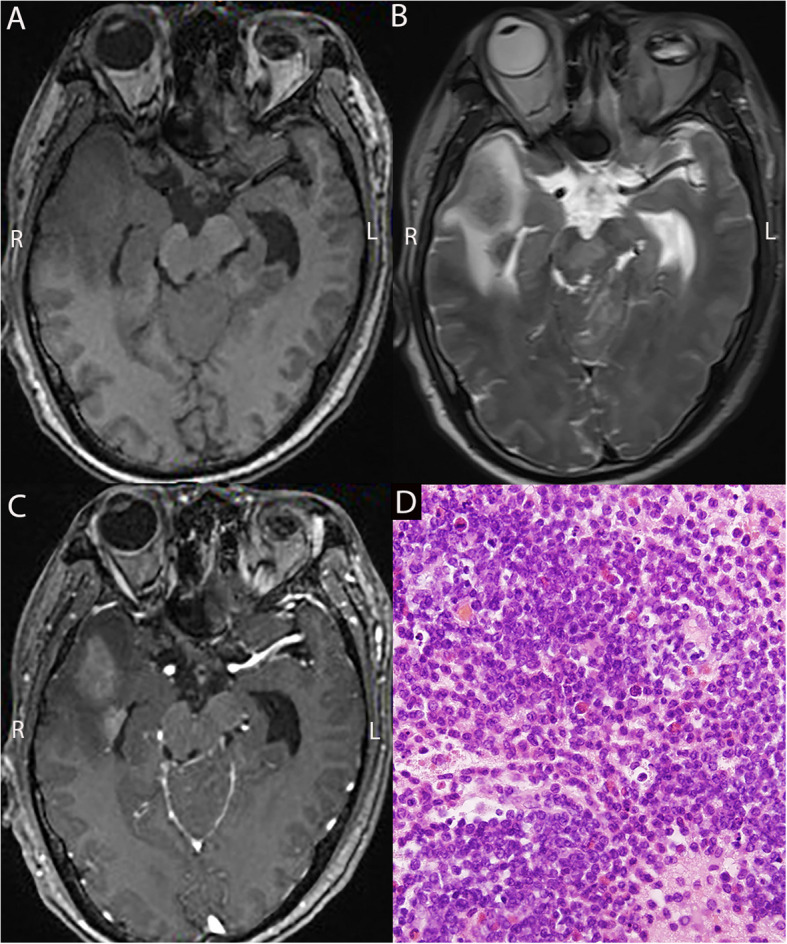

Methods: We retrospectively collected clinical data from 22 patients with LCL and analyzed their magnetic resonance imaging and pathological characteristics. Pathological diagnoses were made using stereotactic intracranial puncture biopsy.

Results: Between April 2003 and December 2023, 22 patients with LCL were admitted, including 18 males and 4 females aged 7-71 years. Bone marrow aspiration identified 14 cases of acute lymphoblastic leukemia (ALL), one of chronic lymphoblastic leukemia, six of acute myeloid leukemia (AML), and one of chronic myelomonocytic leukemia (CMML). Most patients presented with non-specific symptoms, including headache, nausea, vomiting, limb convulsions, and changes in mental status. A few patients had localized neurological deficits, such as limb weakness and blurred vision. Common systemic symptoms included fever, night sweats, and weight loss. The pathological diagnoses of the 22 patients were CNSL in 13 patients, CNS infections in five patients, and neurodegenerative diseases in four patients. Discrepancies were found between the clinical and pathological diagnoses in eight cases.